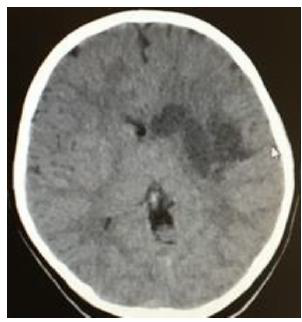

Criança de 8 anos, masculino, branca, acompanhada pela mãe, dá entrada no hospital com afasia mista e hemiplegia a direita. Acompanhante relata que a paciente estava previamente hígida e após atividade física, torneio de basquete e natação que ocorreu na escola do dia anterior (entre 09:00 - 12:00), a paciente se queixou de cefaleia de intensidade acentuada, não soube especificar o tipo e se havia irradiação, associada à dor torácica e dispneia. A mãe a medicou com dipirona, 40 gotas, e a paciente dormiu. Quando despertou às 16 horas apresentava afasia motora e choro gesticulando que permanecia com dor torácica. A mãe fez então massagem com hidratante corporal em todo o corpo da paciente e administrou ½ comprimido de Torsilax®, após isso a paciente adormeceu. No dia seguinte, em torno de 7h a mãe a encontrou caída no chão aos pés da cama, afásica, com desvio da rima labial para a esquerda, hemiplegia à direita e disfagia, teve insucesso na tentativa de levantá-la. Foi então que a levou à Unidade de Pronto Atendimento (UPA) onde foi encaminhada para o Hospital Universitário, lá realizou exames. A paciente apresentava hemiplegia direita e afasia mista e queixava de cefaleia e dor toráxica. Ao exame: pele íntegra, afebril, PA: 120X63 mmHg, FC: 72bpm, FR: 14irpm, SatO2 de 100%, pupilas isocóricas, reflexo fotomotor presente, escala de coma de Glasgow com 11/15 pontos. Sintomas Gerais: Refere ao aumento do peso de 15kg em 1 ano e meio. Nega febre, calafrios, prurido, sudorese ou palidez. Refere à cefaleia e dor ocular, nega redução da acuidade visual, fotofobia ou secreção lacrimal. Refere à otalgia e nega otorragia, hipoacusia e zumbidos. Nega epistaxe, rinorreia e parosmia. Refere a palpitações e dor torácica. Refere à dispneia sem tosse e sem hemoptise. Refere à disfagia e nega náuseas ou vômitos. Nega diarreia ou sintomas urinários. Refere-se também à parestesia braquial e crural esquerda. Nega tremores, convulsões e automatismos. Cartão vacinal atualizado. Durante a investigação foi realizado uma tomografia computadorizada (TC) de crânio no 1º DIH com áreas hipoatenuantes mal delimitadas acometendo substância branca e cinzenta das regiões nucleocapsular, insular/subinsular e frontotemporal à esquerda associadas à redução de amplitude de sulcos corticais e fissuras regionais e a compressão de parte do ventrículo lateral esquerdo. Linha média centrada (Figura1).

(Figura1)